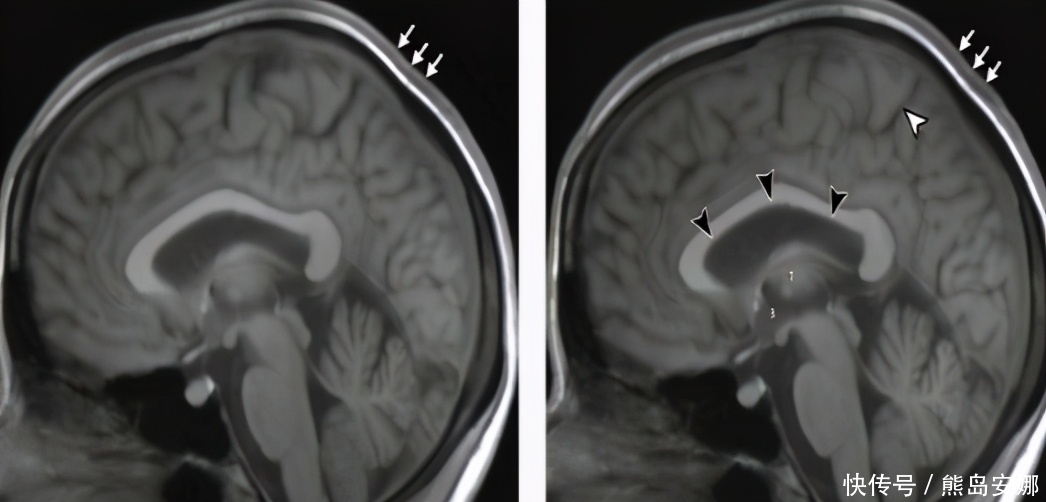

对此北美放射学会的科研人员也着手展开调查,结果表明,虽然这些宇航员在回归地球后经过特殊治疗,90%以上的基因都恢复正常标准,但是有7%却出现永久性的变化,有可能造成难以孕育甚至不孕不育等问题,这也就代表太空中,人类生育能力可能会受到影响从而下降。除此之外在无重力环境下人们会出现颅内高压的情况,导致体内身体结构出现变化。